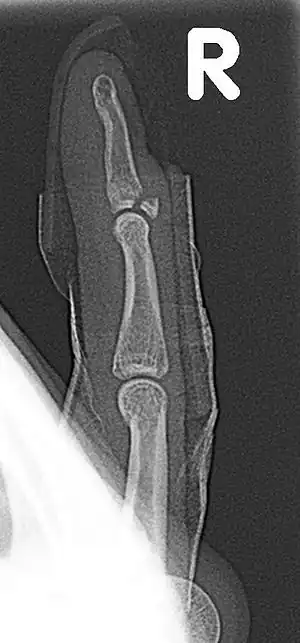

| Fracture of the dorsal base of the distal phalanx by extensor tendon avulsion (Busch fracture) | |

Busch fracture, also known as baseball finger, is a type of fracture of the base of the distal phalanx of the finger, due to being pull on by the extensor tendon.[1][2] Without treatment, a hammer finger may result.

It is common in motorcycle riders and soccer joggers, caused by hyperflexion when the tendon is exercising its maximum tension (the closed hand tightening the clutch lever or the brake lever).[3][4] The underlying mechanism is an avulsion fracture of the distal phalanx by the attached tendon.[5][6][7] It corresponds to the group B of the Albertoni classification.[8]